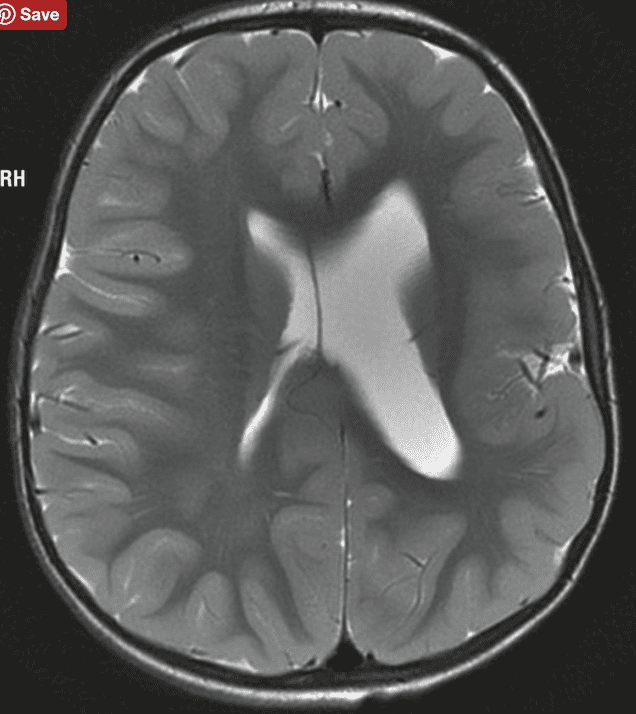

The next day was in another hospital: an MRI scan of the entire body and brain, a cardiology test, breast research and some other stuff. I was a bit nervous about the MRI. I am very sensitive to electro magnetic fields. How would I feel about going into this electro magnetic tunnel, not being able to move for 45 mins? And what about the contrast liquid they would put into my body? I felt slightly nauseous, just thinking about it. Fortunately the doctor recommended doing the MRI without contrast liquid, since it was preventative and we were not looking for something specific. A few minutes later I found myself being prepared to go into the MRI ‘tunnel’. It is interesting that if you do this as part of a prescan, you feel completely different than when you are sick. No nervousness about what they are going to find, no discomfort, no stress, just a mild curiosity. The sound the MRI makes is very loud. Like standing in front of the speakers of a techno festival… Strange enough, it kind of relaxed me. I had no problems at all being completely immobile for 45 mins. Weird, because when I try to meditate, I can’t sit still for 5 minutes! Afterwards the radiologist explains the 1500(!) MRI pictures taken of my body and brain. Except for some small damage from the whiplash, visible in my brain, there is nothing remarkable. Alzheimer’s not measurable on MRI, unfortunately. Oh, by the way, he mentions that my brain has asymmetric brain ventricles (fluid chambers). Normal ventricles look something like the first picture and mine look more like the second one (but then reversed: my ventricles are on the left side of my brain):

He explains this has been the way like this since I was born and it’s nothing to worry about. He also says it is not quite common. Anybody has any information on this?